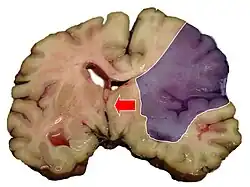

Einteilung nach Infarktmuster in der Bildgebung

Es kann zwischen Territorialinfarkten, Grenzzoneninfarkten und lakunären Infarkten unterschieden werden.

Territorialinfarkte entstehen durch embolischen Verschluss hirnversorgender Arterien und betreffen das Versorgungsgebiet (Territorium) des Gefäßes. Lakunäre Infarkte sind kleiner als 1,5 cm. Sie entstehen meist durch mikroangiopathische Veränderungen. Grenzzoneninfarkte sind hämodynamischer Genese. Sie entstehen meist durch Verschluss der großen extrakraniellen Gefäße oder durch einen passageren Blutdruckabfall bei vorbestehenden Einengungen der Halsschlagadern.[9]